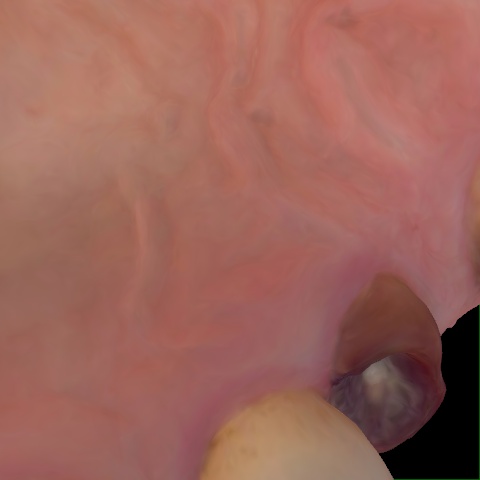

Annotated as "Good"